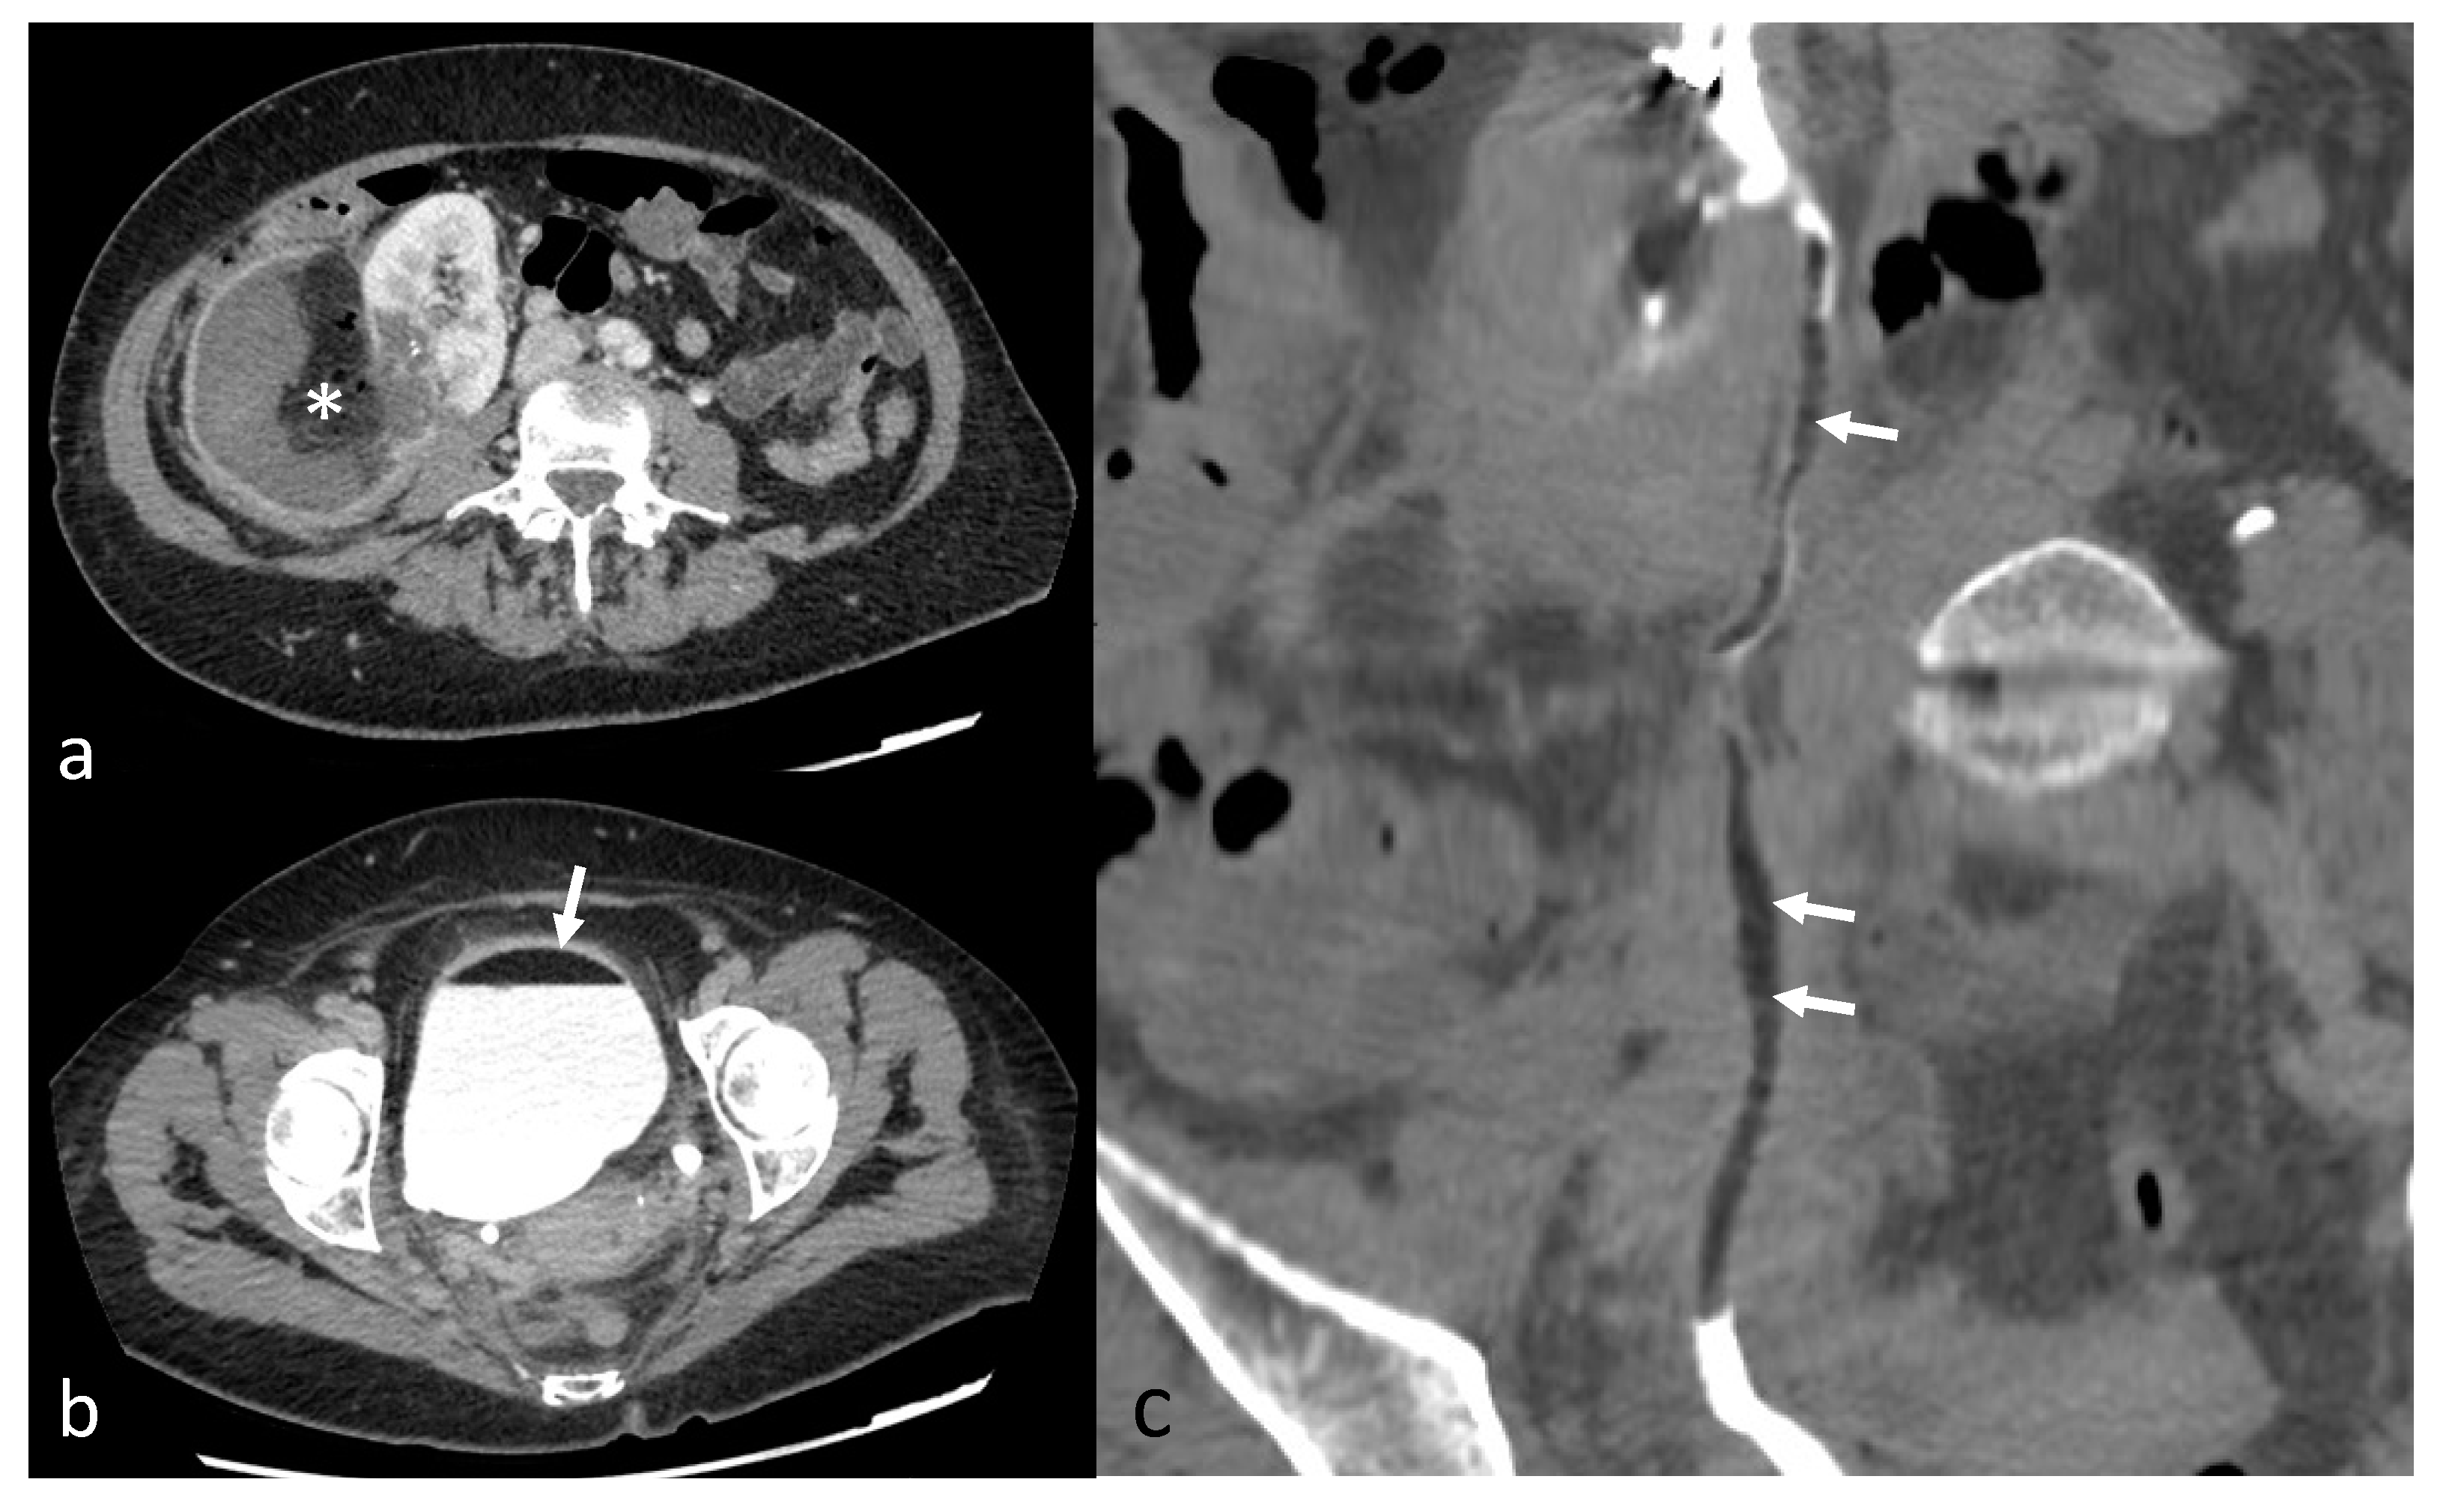

Figure 1.

A 70-year-old patient with right AML (*), Wunderlich Syndrome and aneurysm (white arrow). (a) Yellow ROI showing retroperitoneal hemorrhage (65 UH) on axial computed tomography without injection; (b) Axial computed tomography with injection and arterial acquisition; (c) Coronal computed tomography with injection and arterial acquisition.

AML were diagnosed on the basis of macroscopic fat content and the absence of calcification or necrosis at computed tomography (CT; <−20 Hounsfield Units, HU) or magnetic resonance imaging (MRI; cancellation of a high-intensity signal on T1-weighted MR images with fat saturation) [6], before treatment (Figure 1). In the absence of macroscopic fat, the use of in-phase/opposed-phase sequences, low T2W and/or ADC signal, and avid early enhancement with wash-out kinetics with or without intratumoral microscopic fat on chemical shift imaging was used for diagnosis of renal AML without visible fat [21]. In doubtful cases, a biopsy was performed (1 case). To determine the volume of AML, we used three orthogonal diameters (d1, d2, d3) measurements recorded on radiologic investigation (CT or MRI) before embolization and on the most recent CT or MRI obtained during follow-up after embolization. The AML volume was considered ellipsoid, and we used the formula as follows: (d1 × d2 × d3 × π/6) [22]. Aneurysms were diagnosed and measured on diagnostic imaging studies performed with injected contrast material (Figure 1). Patients were referred to an interventional radiologist for embolization after clinical evaluation by a urologist. Indications for TAE were an AML size threshold of greater than 40 mm maximal diameter, an aneurysm of 5 mm or greater or acute hemorrhage from an AML of any size.

The average arterial pedicle per AML was 1.4 (±0.8). Arterial pedicle count was the number of angiographically visible arterial pedicles that were a direct division of the renal artery and participated in the vascularization of the tumor. A high arterial pedicle count was significantly predictive of a second embolization (p < 0.01). The mean pre-embolization volume was 201.1 (±504.1) mm3. The majority of angiomyolipomas were exophytic (96%, n = 24). Ten patients had aneurysms on angiography (Figure 2a and Figure 3), including only five seen on pre-embolization imaging at diagnosis (Figure 1). Table 2 presents the different AML characteristics.